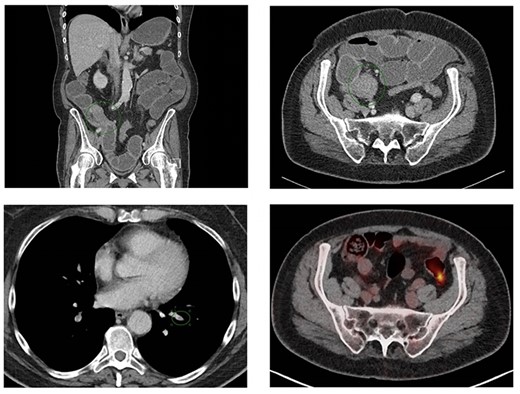

The patient was admitted to the emergency department 23 days after the oncoplastic breast surgery. She presented with abdominal pain, nausea, emesis and stool changes. General examination was normal and vital signs were normal except tachycardia. Abdominal distension, high-pitched tinkling bowel sounds and epigastric tenderness were observed. Laboratory tests revealed a white blood cell (WBC) count of 8.8*10E9/L and C-reactive protein (CRP) level of 19.4 mg/L. Abdominal computed tomography (CT) scan showed a short bowel obstruction caused by a stenosis in the terminal ileum and ileocecal junction without lymphadenopathy signs or metastasis. The basal lung segments were suspect for bilateral pulmonary embolisms (Fig. 2A–C), which was confirmed by a thoracic CT angiography. Retrospectively, an ileocecal tumor could not be identified on a follow-up PET/CT scan which was performed 7 weeks prior to emergency room presentation (Fig. 2D).

Coronal (A) and axial slice (B) of the abdominal CT scan at ER presentation showing small bowel obstruction with terminal ileum (green ellipse) and ileocecal junction stenosis. (C) CT scan at ER presentation also showed pulmonary embolisms in basal lung segments bilaterally (green ellipse). (2D) PET/CT performed 7 weeks prior to ER presentation showed no 18FDG uptake terminal ileum or ileocecal junction.